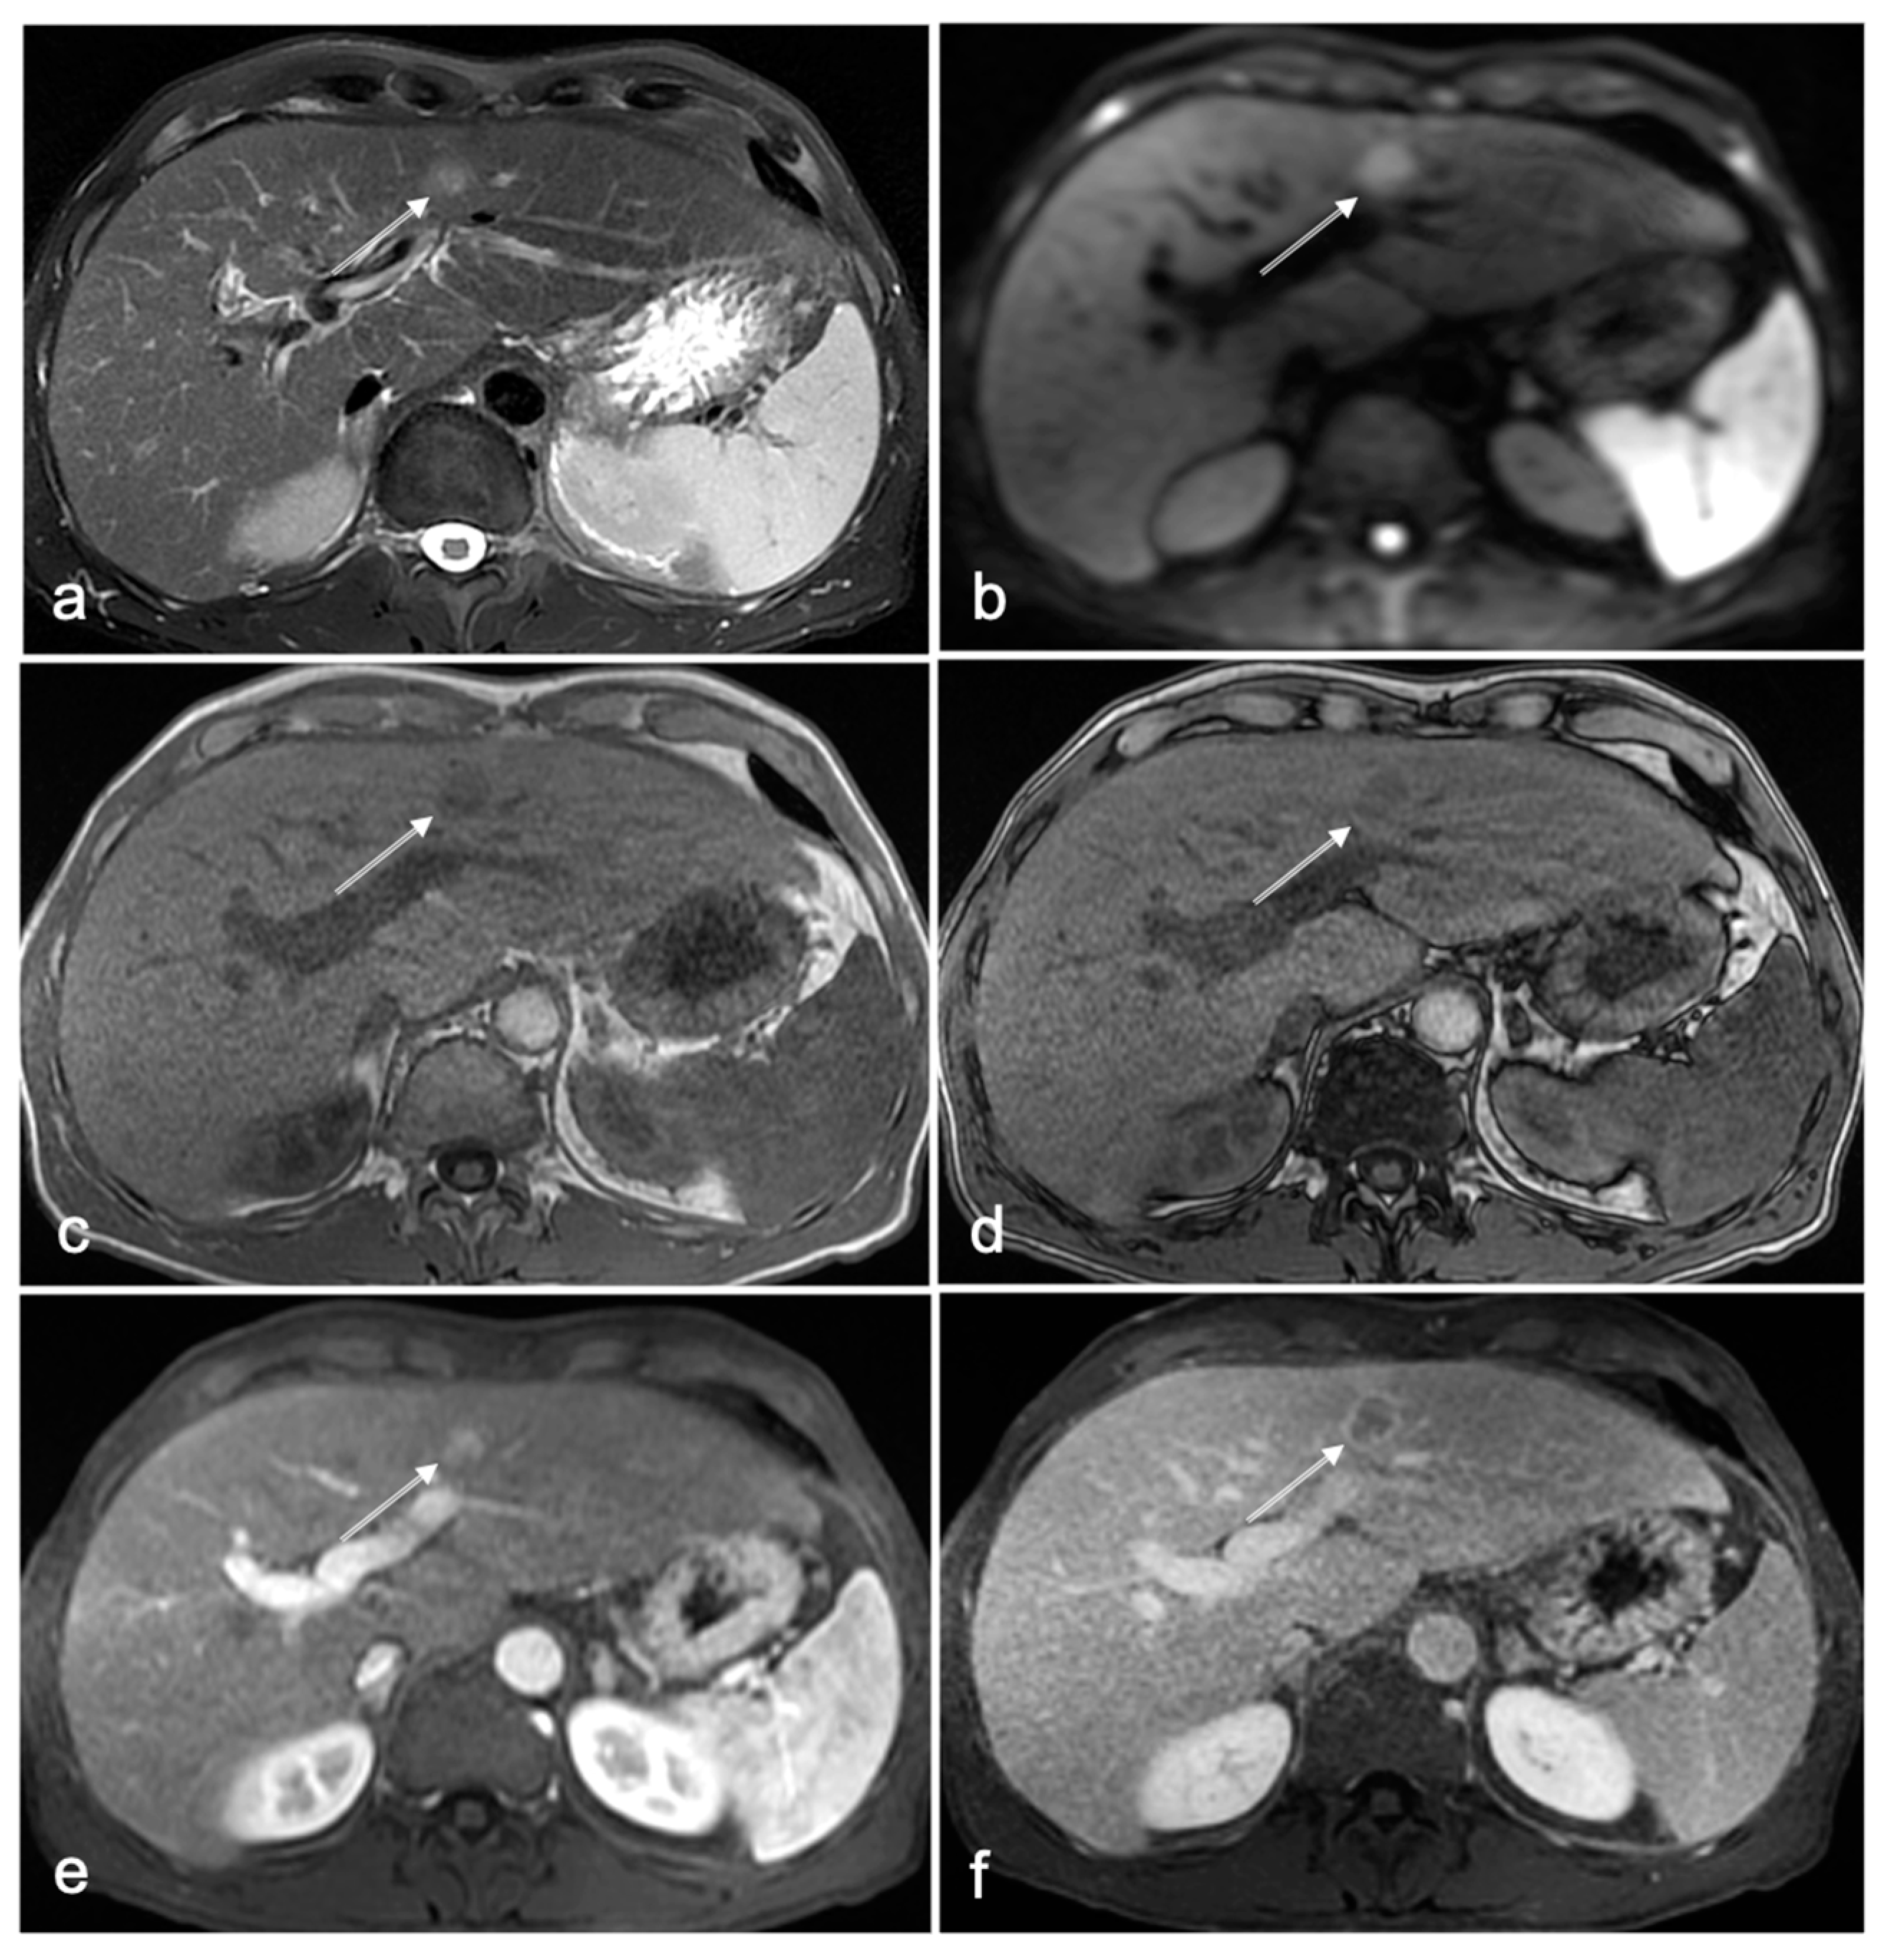

3.1. Cases with HCC